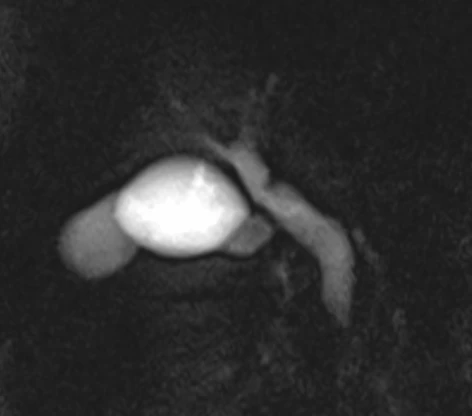

Снеговики бывают разные, но смысл симптома при аденоме гипофиза от этого не меняется: когда опухоль растёт вверх, она протискивается черезу дуральную селлярную диафрагму и в этом месте на ней явственно определяется поясок. Это, как утверждается, достаточно надёжный дифференциально диагностический признак (точность порядка 94-96%) именно аденомы гипофиза, а не какой-то другой опухоли данного расположения.